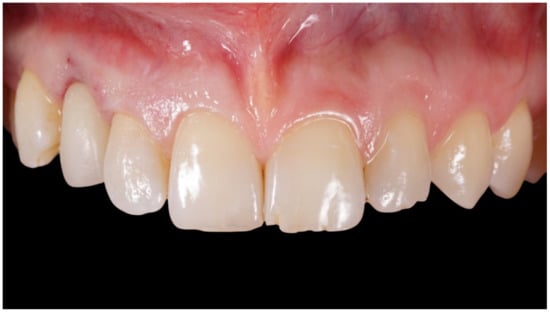

Figure 1.

Preoperative frontal view.